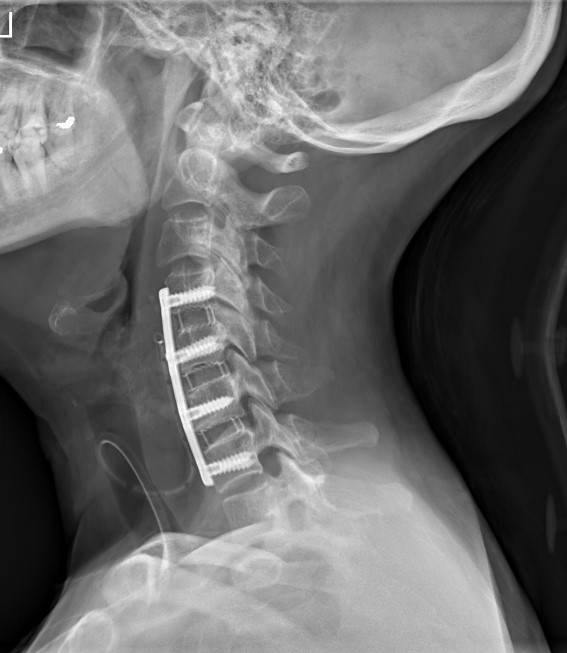

Krční páteř

Krční páteř operujeme nejčastěji z předního přístupu. Příčným řezem v tzv čárách štěpitelnosti kůže (vráskách) se dostaneme k postiženému segmentu páteře. Po odstranění meziobratlové ploténky a osteofytů, které utlačovaly nervové struktury nahradíme vyplníme meziobratlový prostor implantátem vyplněným kostním štěpem odebraným z lopaty kosti kyčelní a obratlová těla fixujeme speciální krční dlahou.

V případech víceetážového postižení krční páteře volíme operační přístup zadní.